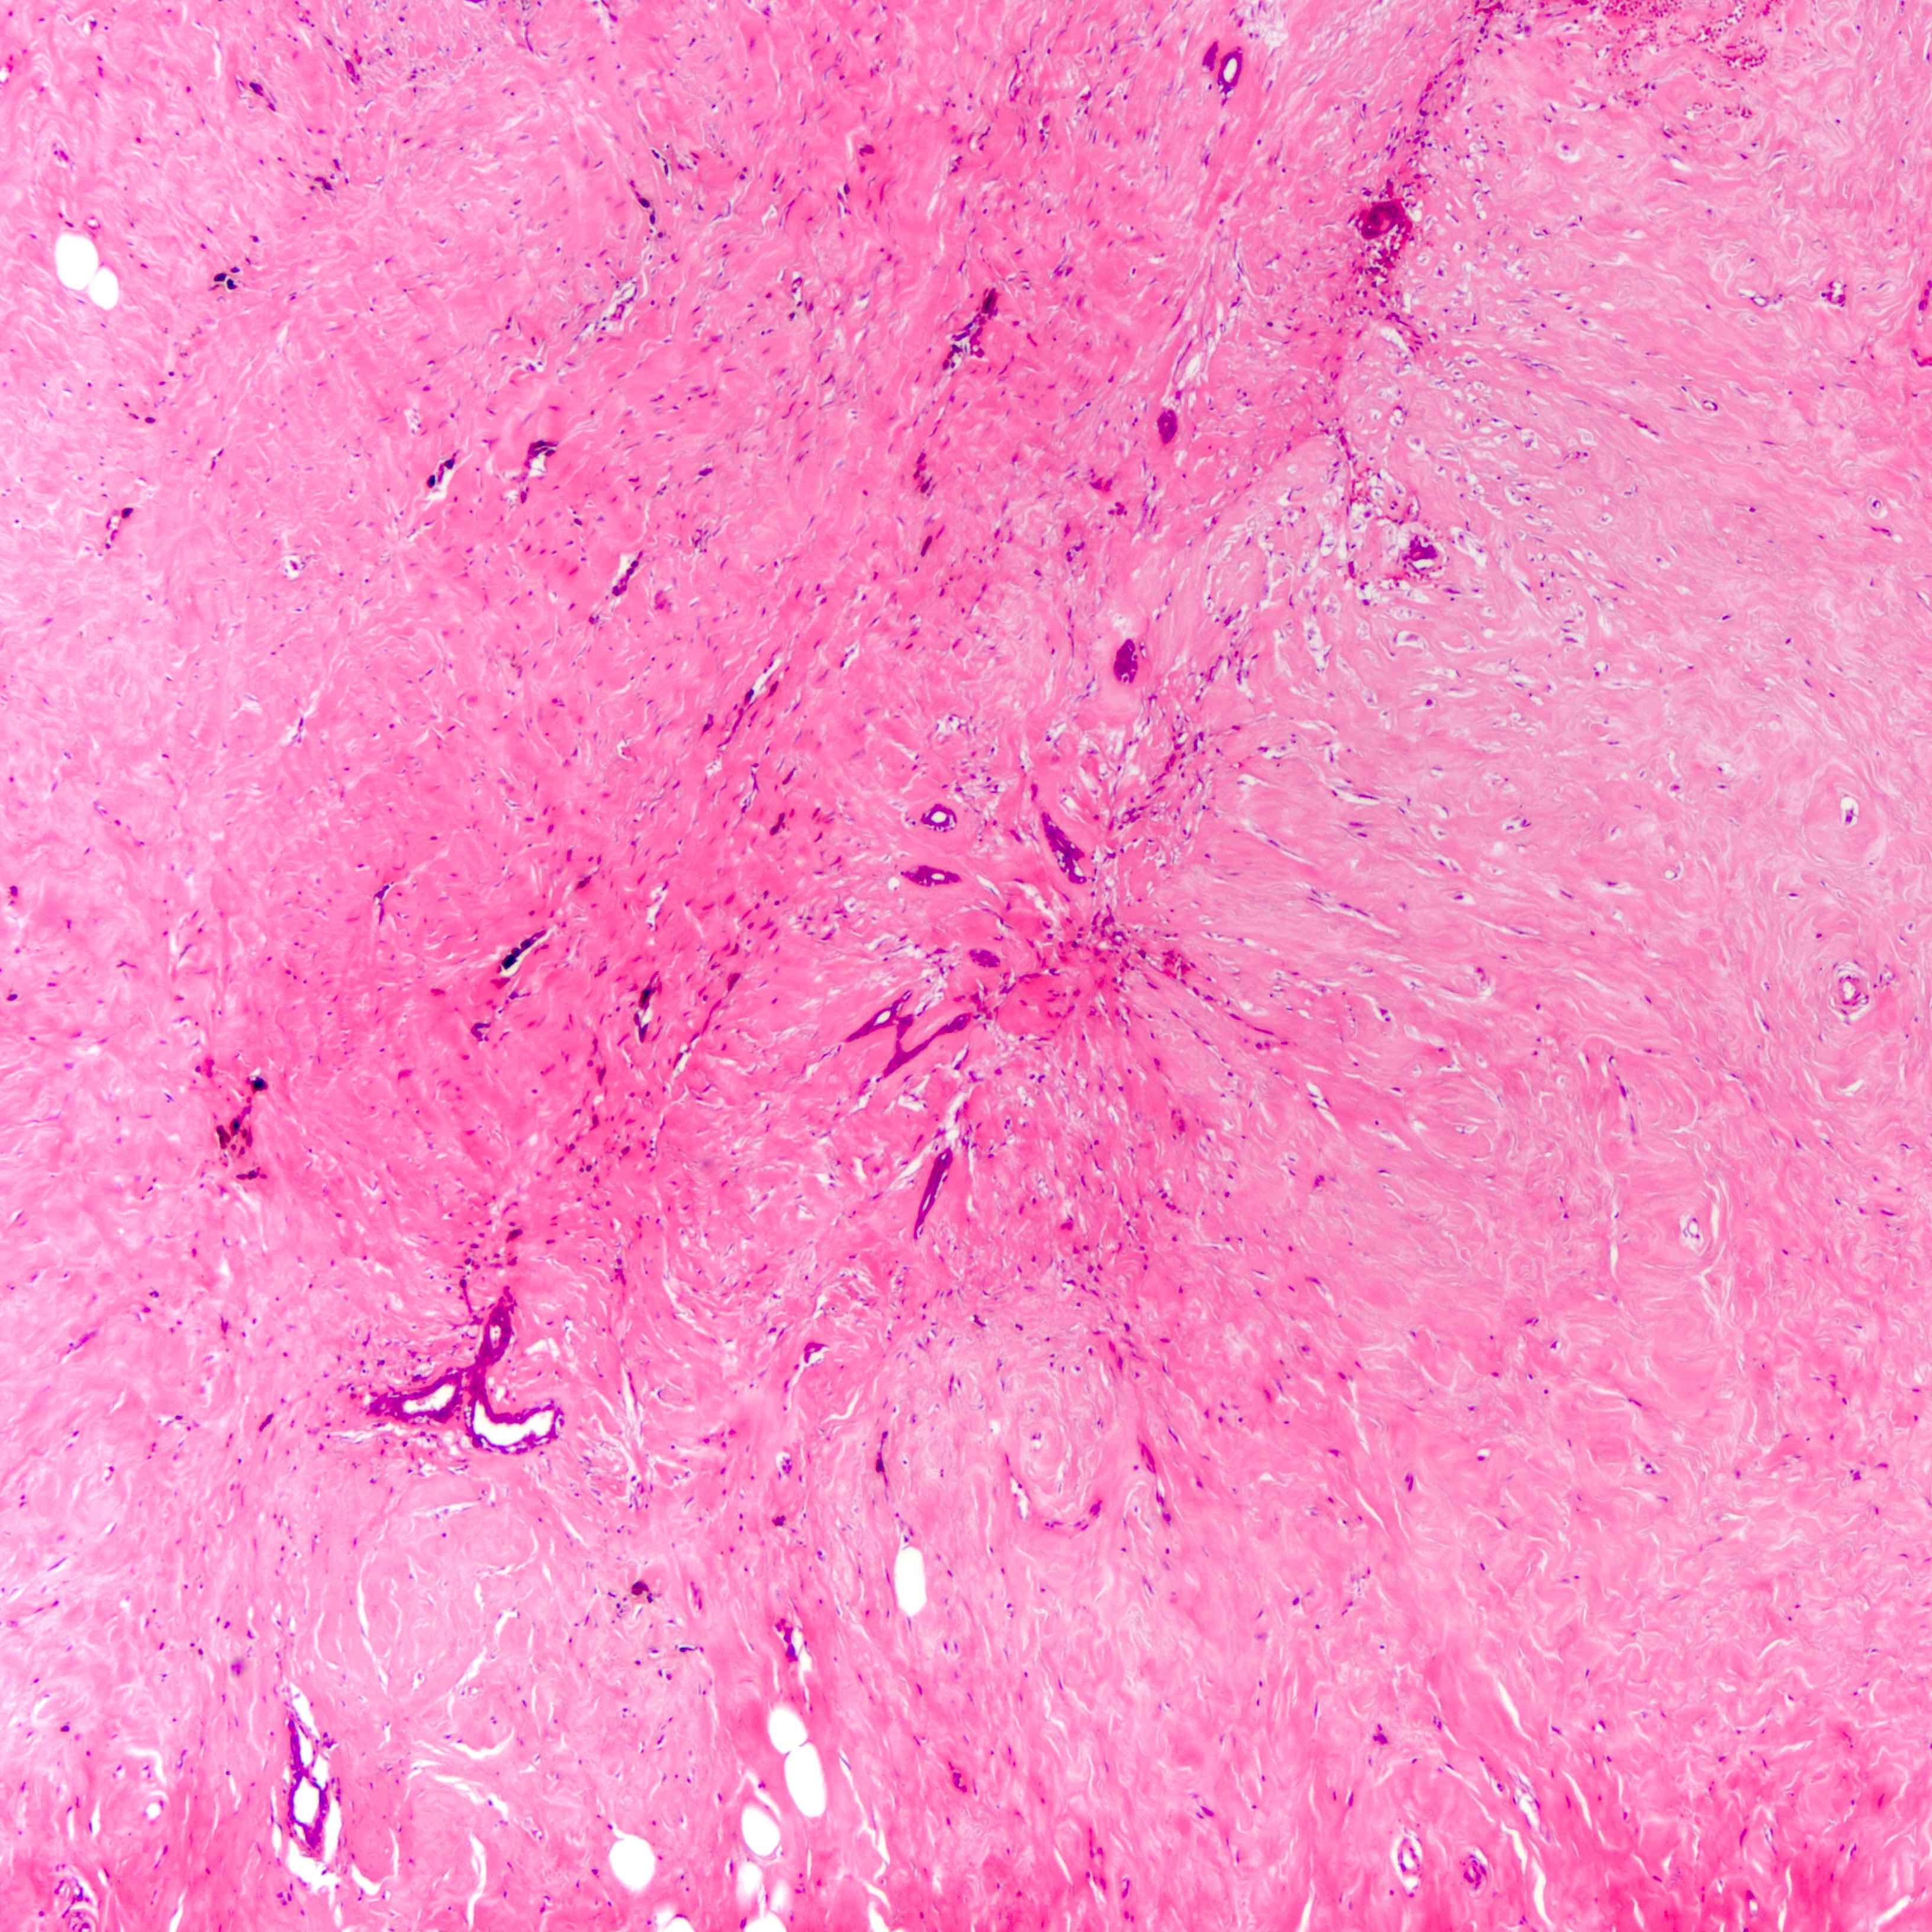

- Histologic evidence of tumor response includes fibrosis, hyalinization, lymphohistiocytic infiltration, hemosiderin laden macrophages, giant cell formation and vascular proliferation

- These histologic features are indicative of the tumor bed

- Patterns observed in partial response includes concentric tumor shrinkage, reduction in tumor cellularity and scattered multifocal tumor deposits (Mod Pathol 2015;28:1185)

- Tumor cells show degenerative changes including nuclear and cytoplasmic vacuolation, karyorrhexis, karyolysis and pyknosis (Int J Appl Basic Med Res 2012;2:111)

- Normal breast tissue shows ductal and lobular atrophy, atypia and hyalinization of vessel wall

Microscopic (histologic) images

Contributed by Joshua J.X. Li, M.B.Ch.B., Gary M. Tse, M.B.B.S. and Emily S. Reisenbichler, M.D.